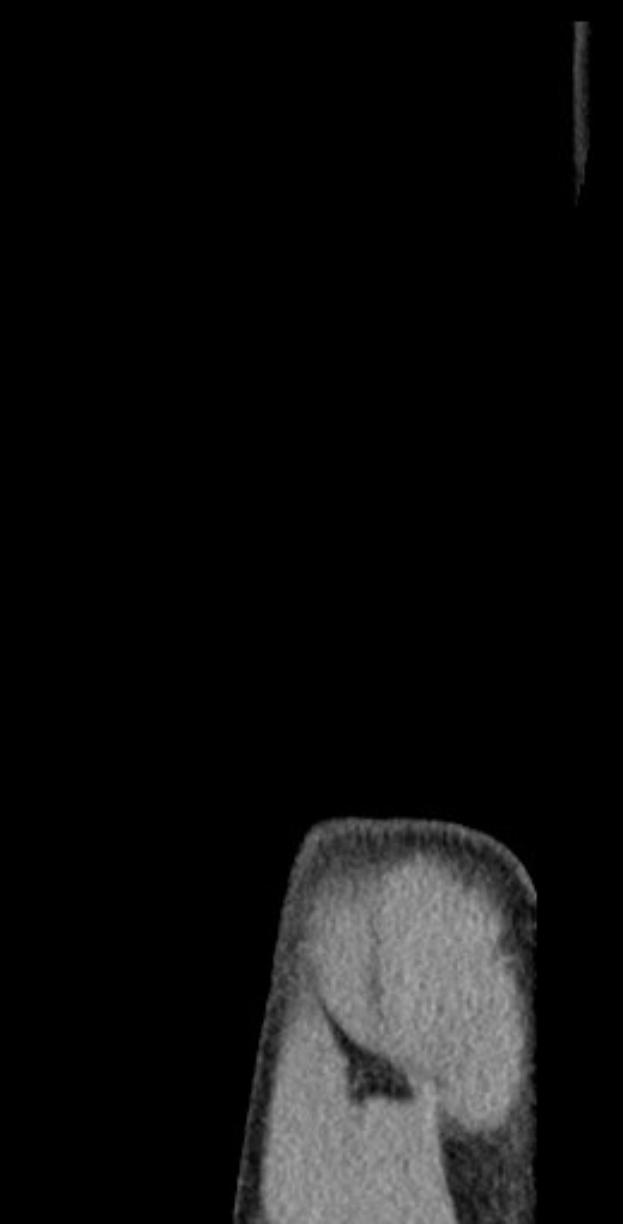

Gechter musste das U21-Qualifikationsspiel wegen Schulterbeschwerden vorzeitig verlassen. Eine sofortige Diagnose gab es nicht, doch der Verein bestätigte, dass ein MRT ansteht. Dies folgt auf eine längere Verletzungspause in der vergangenen Saison, die durch ein ähnliches Problem verursacht wurde.